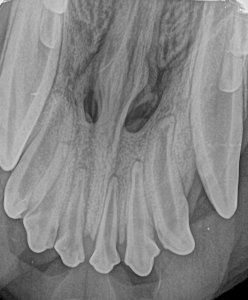

Canine Full Mouth Radiograph Example